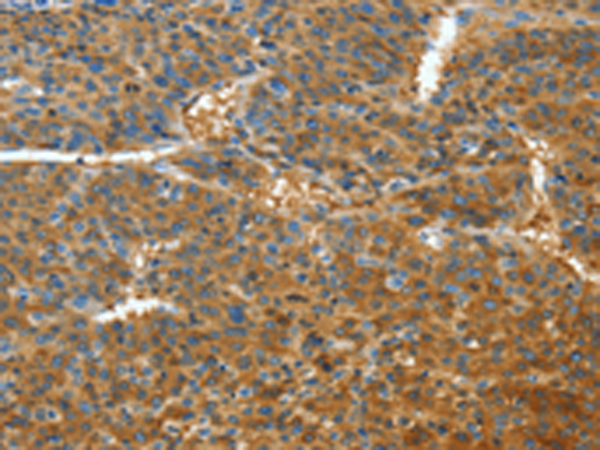

分类: 科研抗体货号: P07118别名: APPL; DIP13alpha应用: WB,IHC反应种属: Human, Mouse